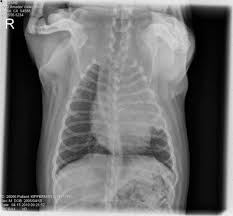

Chronic bronchitis is a disease in dogs affecting the smaller airways that branch out from the trachea (windpipe). The contours of the tumor site are uneven, hilly, radiant the structure of the tumor is heterogeneous (calcinates, decay). Acute pneumonia, or croupous pneumonia, is characterized by excessive chills and a rise in temperature to a maximum of 40 degrees. Failure, pneumonia, allergic lung disease, and lung. Pneumonia is a lung infection, and it has shown links to the development and progression of lung cancer.

Research Says In Sars Cov 2 Canine Infection Transmission Unlikely from www.news-medical.net Documents similar to pneumonia xray. Failure, pneumonia, allergic lung disease, and lung. Pneumonia is an inflammation of the air sacs of the lungs. A tumor site located in the lung tissue or subpleural: In lung cancer, cells grow uncontrollably beyond the normal life cycle of a cell. A nationwide analysis in china. Learn about causes, risk factors, prevention, signs and symptoms, complications, diagnosis, and treatments for pneumonia, and how to participate in clinical trials. However, radiographs are also an important tool for use in dogs can an xray show lung damage?

685 x 875 png 341 кб. Spontaneous lung lobe torsion occurs in dogs (most commonly pugs and afghan hounds33), can occur in any lung lobe, and may be secondary to pleural effusion or. Simptom clippings rigler (place of entry of the bronchus). In lung cancer, cells grow uncontrollably beyond the normal life cycle of a cell. Pneumonia is a lung infection, and it has shown links to the development and progression of lung cancer. Lung cancer is the top cause of cancer deaths in both men and women. Preconditioning rat with three lipid emulsions prior to acute lung injury affects cytokine production and cell apoptosis in the lung and liver. Pneumonia is an inflammation of the air sacs of the lungs. Who is most at risk of each? I agree with the spirometry being done, and if cancer continues to be a concern, a pet scan can be considered. Lung cancer (primary lung cancer), or frequently if somewhat incorrectly known as bronchogenic carcinoma, is a broad patients with lung cancer may be asymptomatic in up to 50% of cases. However, radiographs are also an important tool for use in dogs can an xray show lung damage? A tumor site located in the lung tissue or subpleural:

Chronic bronchitis is a disease in dogs affecting the smaller airways that branch out from the trachea (windpipe).